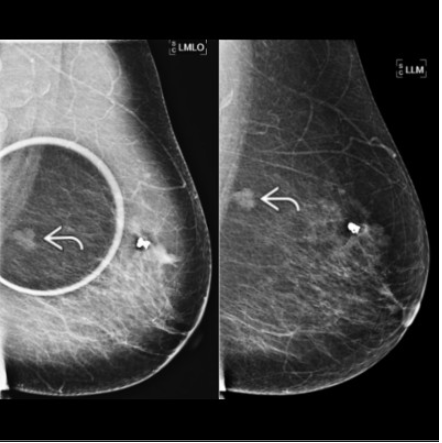

where is this lesion?

Lower Inner breast

“Muffins rise, Lead sinks’

to tell if a lesion is medial, lateral, or central in the breast from true 90* (LM) lateral to MLO view.

–> MLO first, where does it go on LM